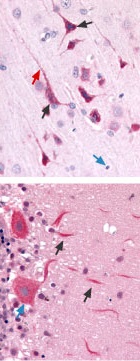

Immunohistochemical staining of CaV3.3 channel with Anti-CaV3.3 (CACNA1I) Antibody(#ACC-009) in in rat brain cortex and cerebellum. (A) Picture showing the third layer of the brain cortex. Pyramidal neurons cells (black arrow) and their axons (green arrow) shows strong staining. However, glial cells (blue arrows) show no staining at all. (B) Picture showing the Purkinje layer of the rat cerebellum. Note that Purkinje cells (blue arrows) and their axons (black arrows) were strongly stained. Staining product is red and counterstain is hematoxylin.

Immunohistochemistry data provided by LifeSpan Biosciences, Seattle, USA.